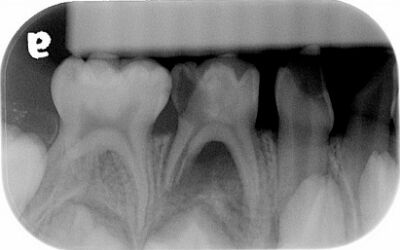

35.5歲男童因右下牙痛求診,拍攝之放射線影像如圖所示;先注射2% lidocaine with 1:100,000 epinephrine後開始後續處置,下列何者錯誤? (A)第一乳臼齒不宜施行活髓治療(vital pulp therapy) (B)第一乳臼齒可考慮拔除 (C)第一乳臼齒牙根吸收非生理性現象 (D)該麻醉藥物的最大劑量是6.0 mg/kg

40.3歲男童因牙齒缺損及變色前來求診,拍攝放射線影像如圖示,下列敘述何者正確? (A)左側上顎正中乳門齒發生牙根內吸收 (B)左側上顎正中乳門齒牙冠應呈粉紅色 (C)此案例牙根吸收的原因可能是外傷 (D)此案例的診斷為根管堵塞(obliteration)